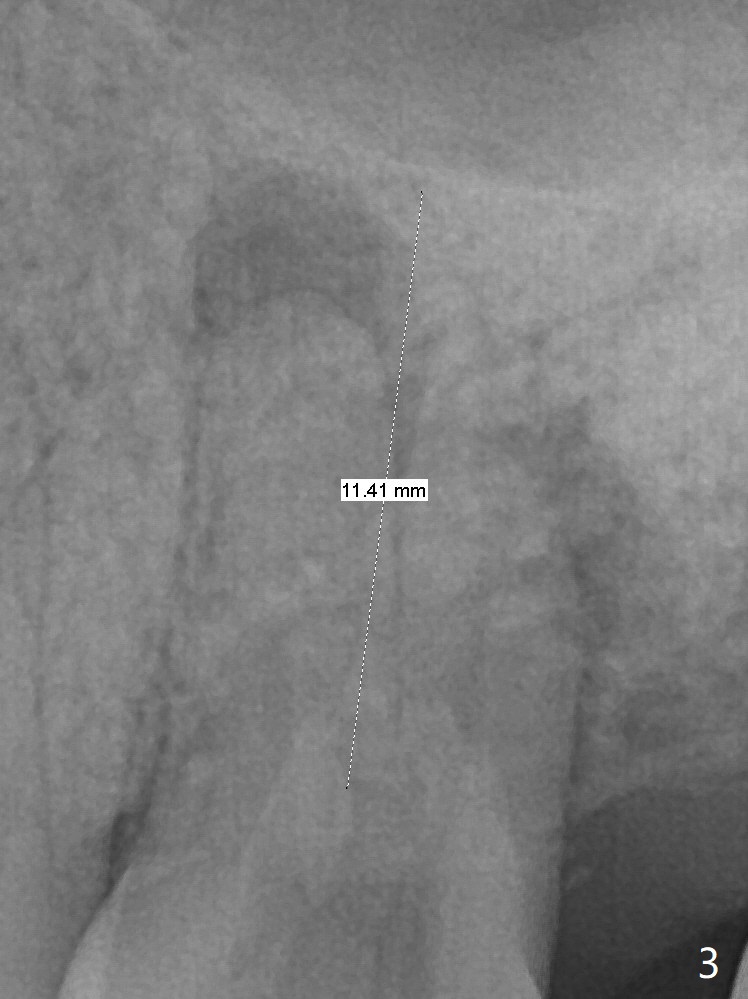

A 59-year-old woman has lost several teeth. The remaining ones are under stress (over-loaded), either severely worn (Fig.1 #31) or fractured (#13). The latter has 2 sockets with severe infection (Fig.2, IS implant). Start osteotomy in the palatal socket. Since the bone height is 11 mm (Fig.3), place PRF and bone graft before a 4x11 mm implant.